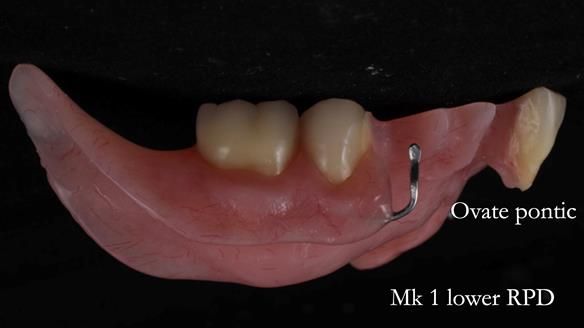

Welcome to my Newsletter 54 showing the making and fitting of dentures (a complete upper metal reinforced denture, a lower immediate partial denture and a definitive Scandinavian designed, metal based lower partial denture) for David, a 75 -year-old man. The full protocol workflow is presented including the use of dentate photographs to mimic his natural teeth.

Interestingly we found that the upper complete denture when finished and fitted didn’t have good enough retention for David’s satisfaction. It was relined by adding compound to the buccal flanges – to almost overextend into the sulcus to ‘create’ a sulcus, followed by using a light bodied silicone impression material. This improved the function of the C/-considerably. A lower Scandinavian hygienically designed lower RPD was also provided which helped with occlusal stability and reseating the upper denture – further improving the fit.